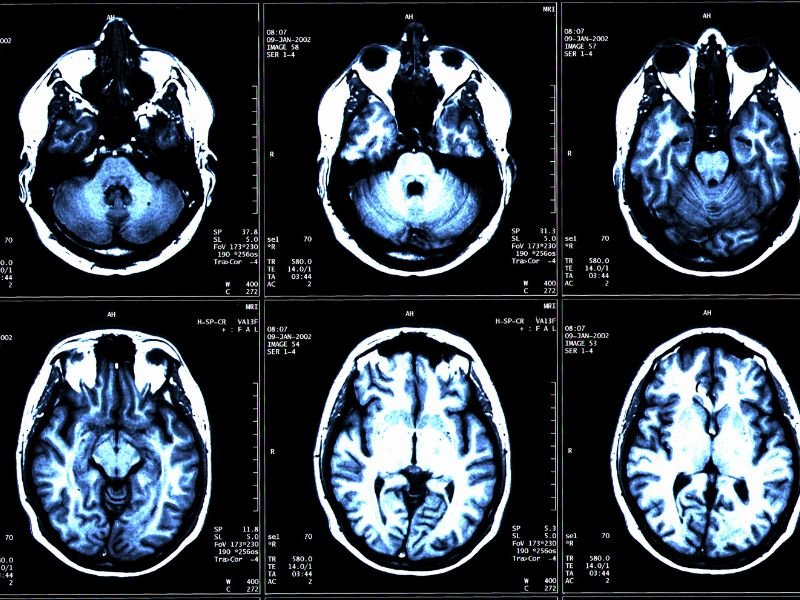

Tratamento de Aneurisma Cerebral em Tubarão SC O aneurisma cerebral é uma dilatação anormal de uma artéria no cérebro, que pode levar a complicações graves, como hemorragias. O tratamento desse tipo de condição é fundamental